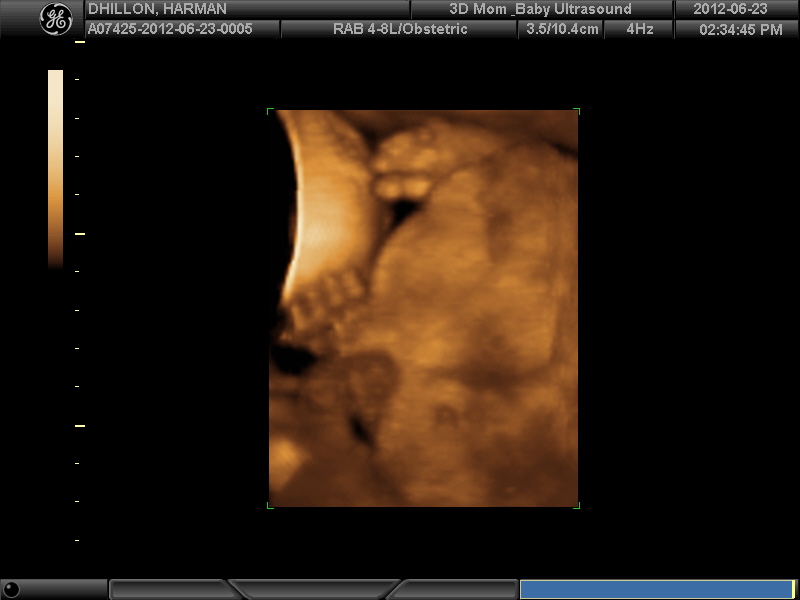

I had a 3D scan yesterday - would love some guesses if possible. Placenta was anterior and hard to find a good position.

Ah sweet baby!

I think 3D/4D images arenīt good for gender guessing, beautiful picture of your babies face anyway.